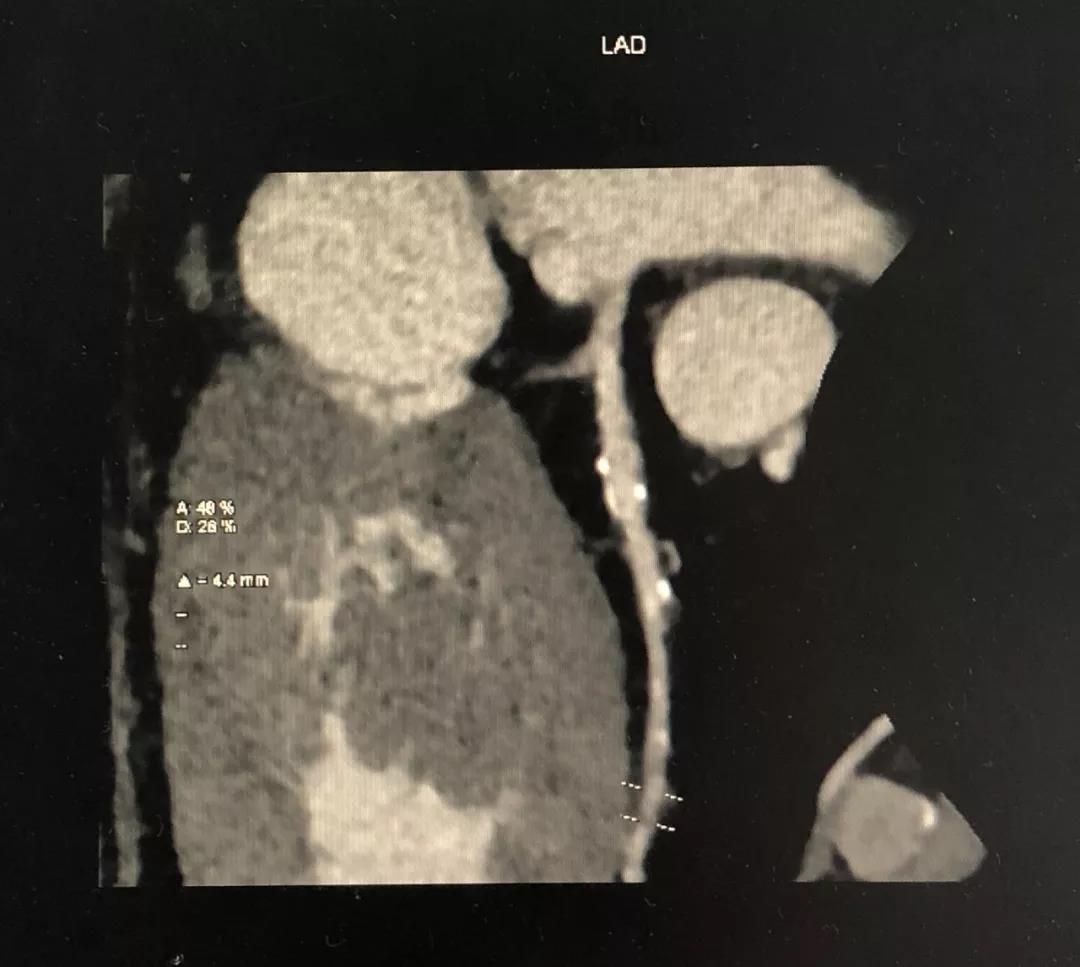

CCTA LAD病变特点:

近段血管较直

中远段血管偏细

中远段血管病变弥漫

病变段扭曲不很明显

病变段无重要分支发出

病变血管段有局灶点状钙化

1、明确了LAD病变位于血管的中远段,比较弥漫,病变段血管整体偏细,是应用药物球囊的适应症;

2、根据CCTA检查的结果,知晓病变的情况,预先准备好相应型号的药物洗脱球囊;

3、病变段血管为局灶性钙化,提示病变的预处理应该会很顺利;

4、病变近段的血管较直,相对健康,药物球囊入路通畅;